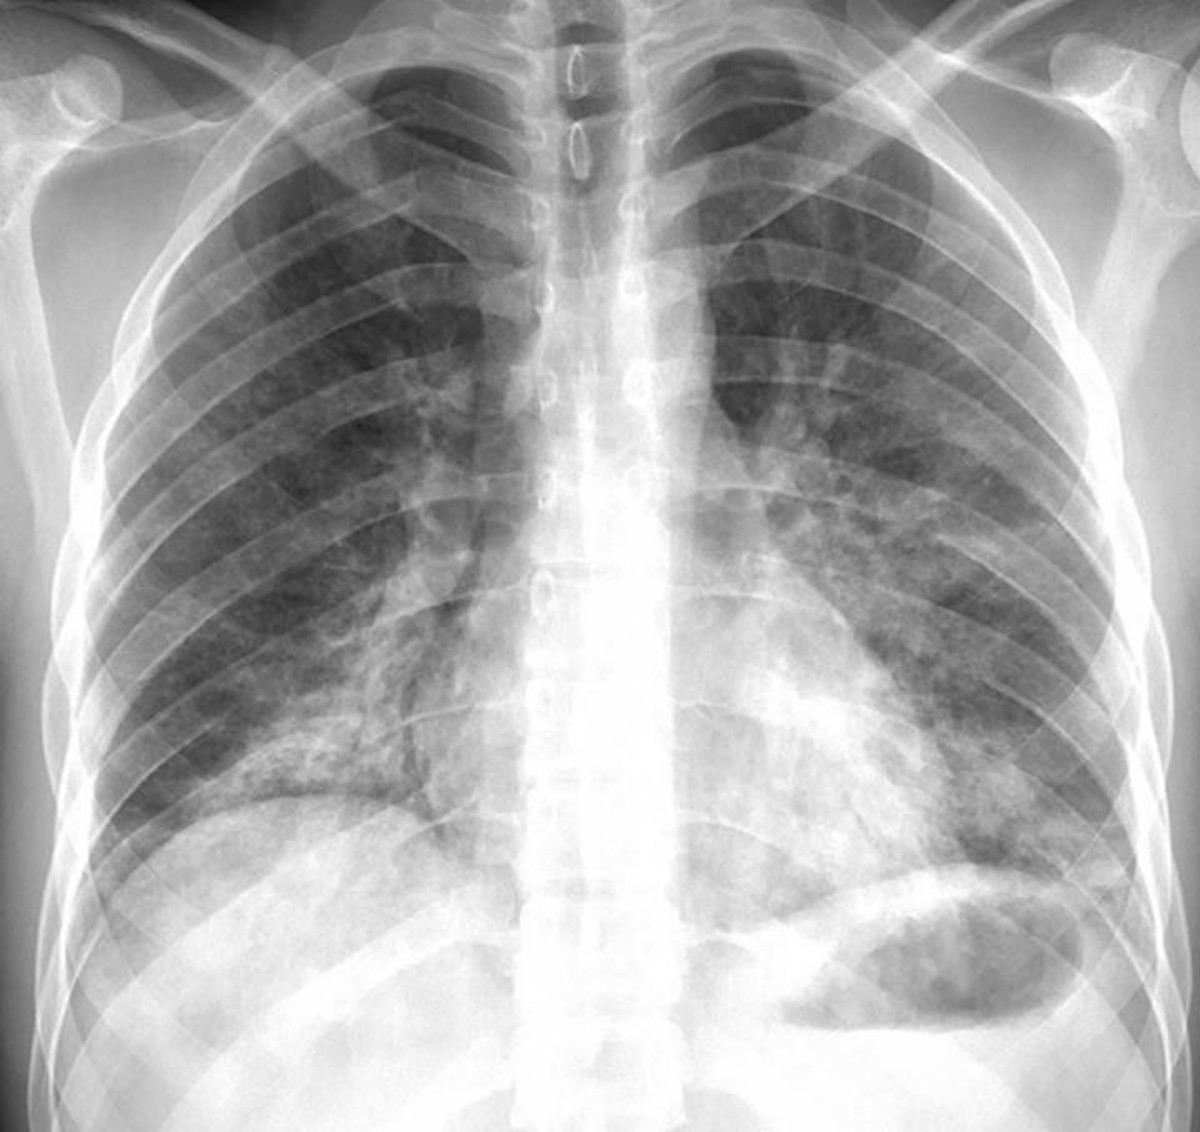

La Deficiencia de Alfa-1 Antitripsina (Alfa-1) es un trastorno que se trasmite genéticamente. Este trastorno puede resultar en serias complicaciones pulmonares en adultos así como también en complicaciones hepáticas y cutáneas serias en bebés, niños y adultos.

Síntomas relacionados con los pulmones:

Falta de aire, sibilancias, tos crónica, flema, fatiga, resfriados frecuentes.

Diagnóstico

El diagnóstico se realiza mediante un simple análisis de sangre que mide los niveles de Alfa-1 Antitripsina.

Es rápido, accesible y puede evitar complicaciones futuras.